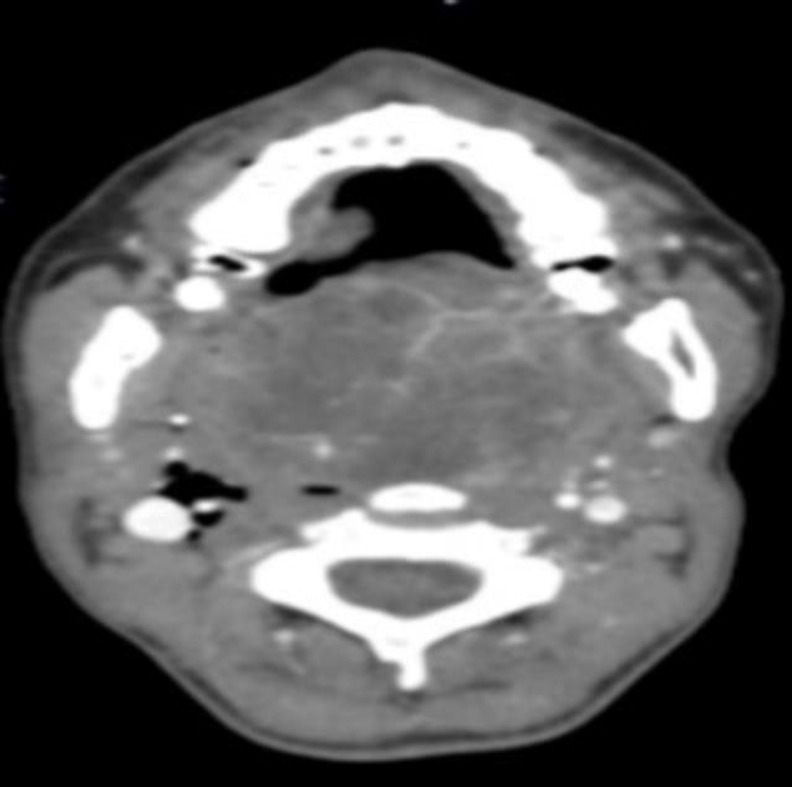

Case report: We described a case of a 39-year-old female presented with a slowly growing mass involving the soft palate. A life-threatening bleeding from PA with hemorrhagic shock occurred and required ligation of the external carotid artery with tracheotomy. A transoral en-bloc excision of the mass (70 x 50 x 40 mm) was performed. Pathological exam demonstrated an atypical PA, with hypercellular fields and myoepithelial and squamous differentiation.